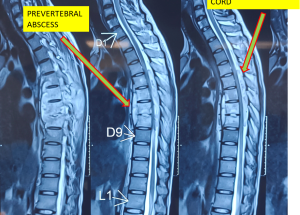

Expert spine services including minimally invasive surgery, pain management, and deformity correction.